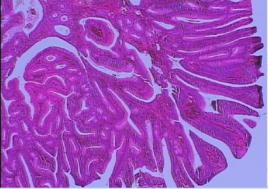

(2)絨毛狀腺瘤:較管狀腺瘤少見,絕大多數為單發。一般體積都較大,直徑大多在1厘米以上,大部分為廣基,約10~20%可以有蒂。表面呈暗紅色,粗糙或呈絨毛狀突起或小結節狀,質軟易碎,觸之能活動,如觸及硬結或固定,則表示有癌變可能。分布以直腸最多,其次為乙狀結腸。組織學表現為上皮呈乳頭樣生長,中心為血管結締組織間質,亦伴隨上皮一起增生,分之成乳頭樣生長,上皮細胞多間變明顯。其癌變率較管狀腺瘤大10倍以上。